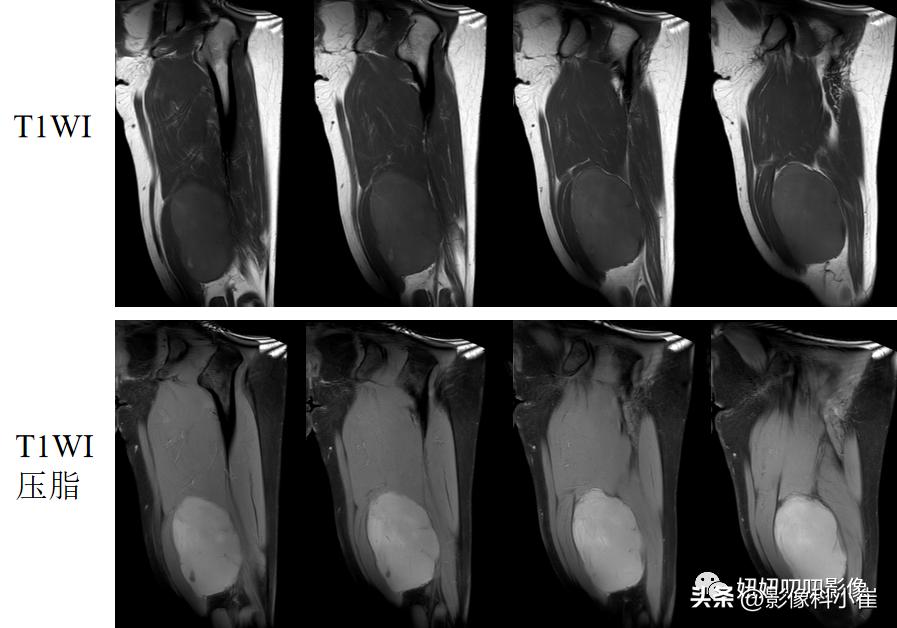

影像描述:

左侧股骨后内侧见卵圆形稍短T1 长T2 信号灶,边界清晰,大小约6.7cmX6.4cm X13.2cm,压脂序列信号强度未见明显减低。内见多发细线状长T1短 T2 信号。DWI 未见明显弥散受限。周围软组织未见明显异常信号灶。